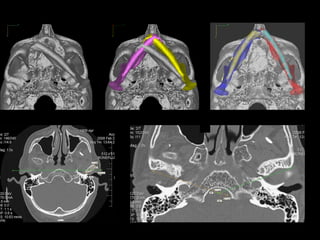

TC 3D

Adquisición de datos Reconstrucción virtual del modelo 3D Validación Validación Producción física del modelo Cirugía de modelo: moldeo placa, osteotomía mandíbula y peroné Esterilización: placa y modelo Uso en quirófano

Adquisición de datos Reconstrucción virtual del modelo 3D Validación Validación Producción física del modelo Cirugía de modelo: moldeo placa, osteotomía mandíbula y peroné. Esterilización: placa y modelo Uso en quirófano

Adquisición de datos Reconstrucción virtual del modelo 3D Técnica de espejo Validación Validación Producción física del modelo Cirugía de modelo: moldeo placa, osteotomía mandíbula y peroné. Esterilización: placa y sistema y modelo Uso en quirófano